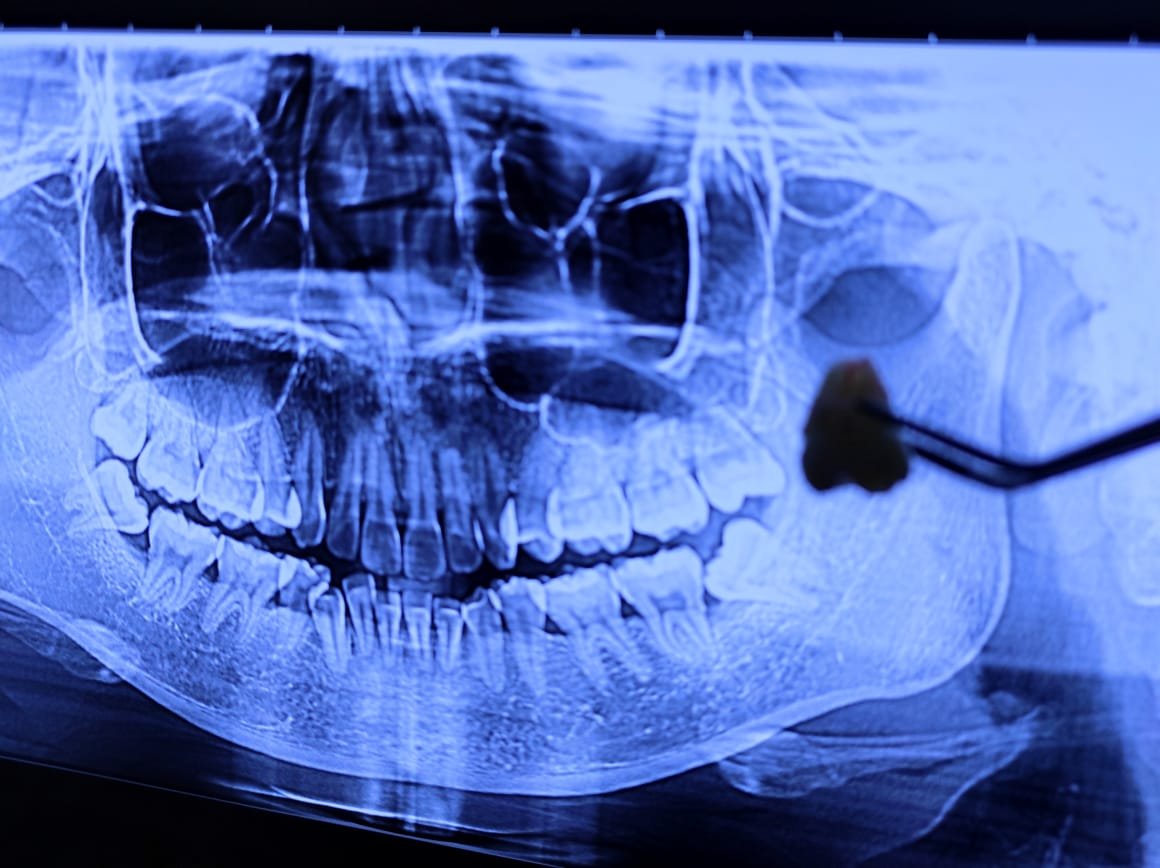

Dokter melakukan rontgen panoramic untuk melihat posisi gigi bungsu dan menilai kondisi pasien.

• Teknologi rontgen panoramic modern.